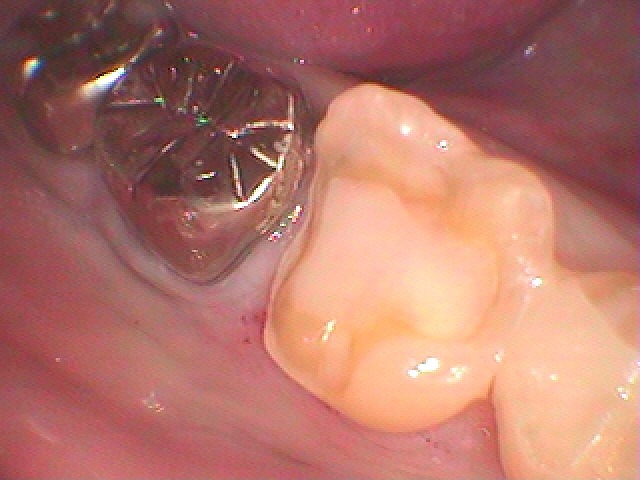

その後ろの右下の6番部も白いセラミックへやり変えたいといわれました

銀歯を外していきました

CR樹脂にて覆罩を行っています

セレックセラミックにて審美的にもきれいに仕上げています